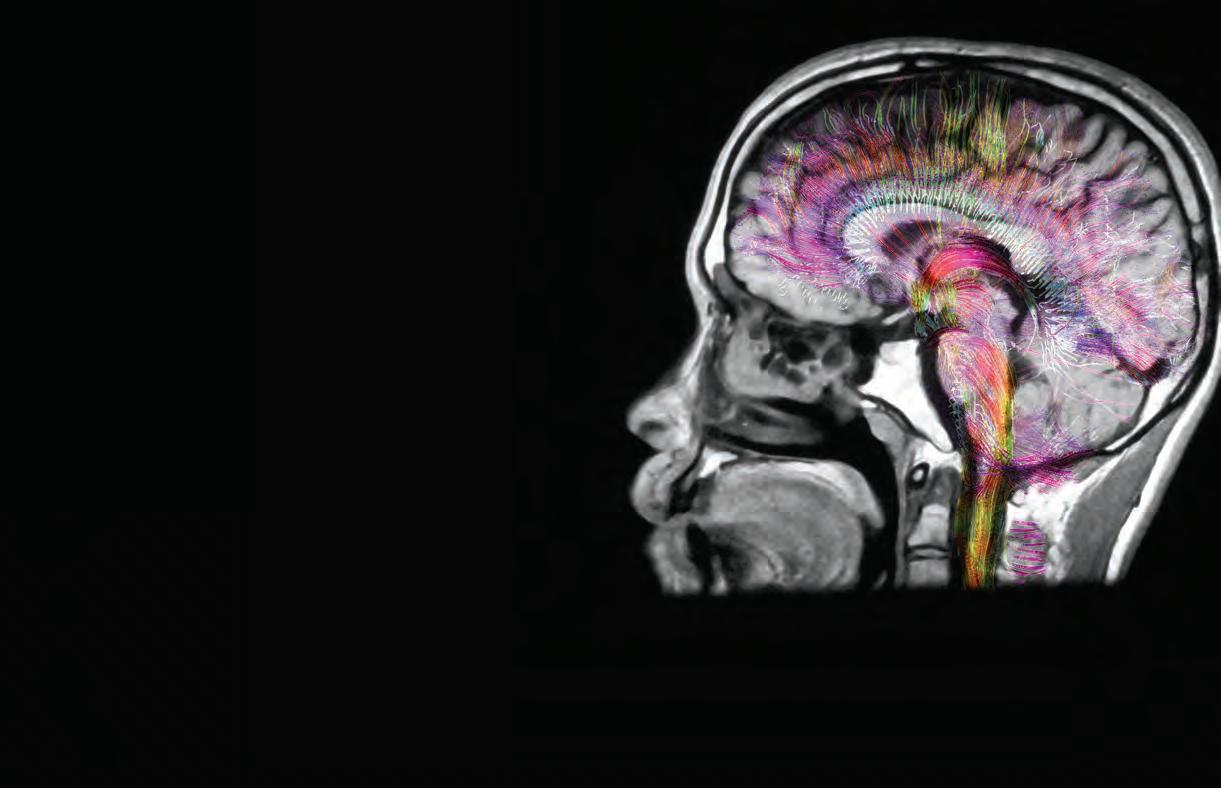

THE ART AND SCIENCE FUNCTIONAL NEUROSURGERY

These highly trained neurosurgeons help thousands of people every year find relief from the often-debilitating effects of epilepsy, essential tremor, Parkinson’s disease, peripheral nerve disease, spinal pain, spasticity and other chronic conditions. “The goal of functional neurosurgery is to minimize symptoms, restore function and give patients their quality of life back,” said Dr. Amir Faraji, functional neurosurgeon with the Houston Methodist Neurological Institute.

WHAT IS FUNCTIONAL NEUROSURGERY?

Functional neurosurgery uses advanced technology, often with implanted devices and new surgical approaches, to stop misfiring pathways of the brain and nervous system that are causing issues. “These procedures allow us to address symptoms that are resistant to traditional therapies and medications or have previously been untreatable. For many people, the results are truly life changing,” Faraji said.

Having access to the latest technology and precise imaging ensures surgeons are hitting the correct area of the brain. “These procedures are performed using advanced surgical robotics and real-time MRI for lead placement, so they are both incredibly accurate and very safe,” Faraji explained.